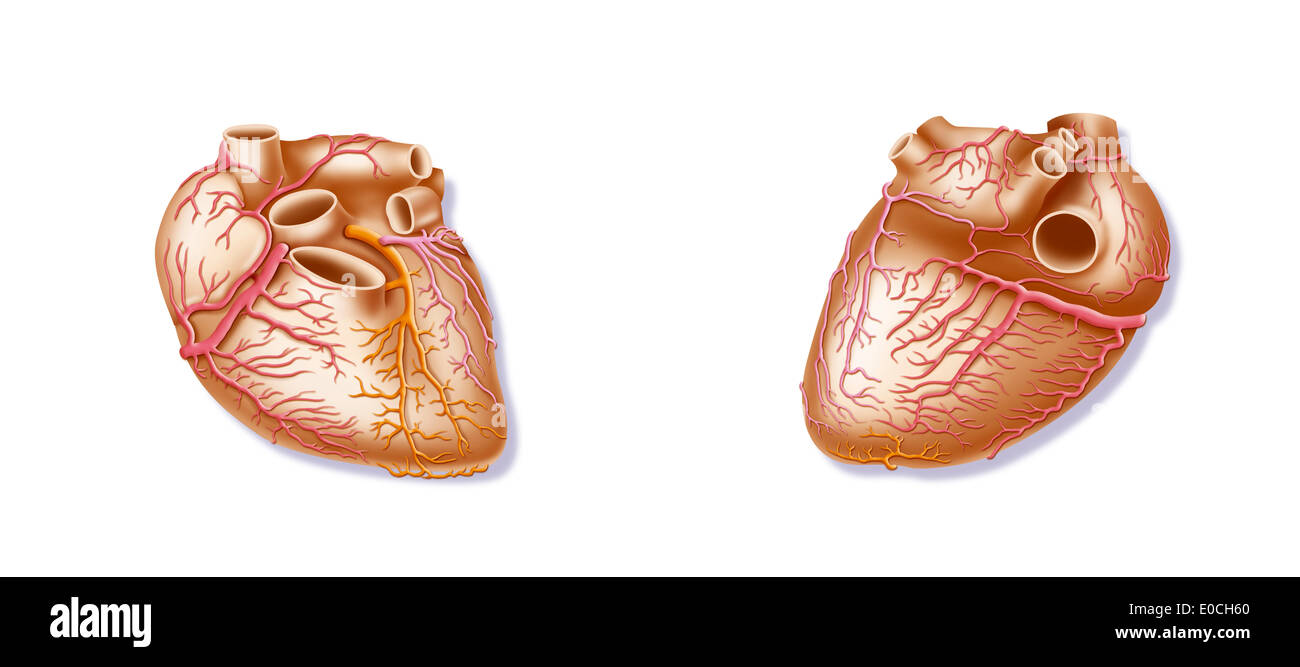

Heart, illustration Stock Photohttps://www.alamy.com/image-license-details/?v=1https://www.alamy.com/heart-illustration-image69118392.html

Heart, illustration Stock Photohttps://www.alamy.com/image-license-details/?v=1https://www.alamy.com/heart-illustration-image69118392.htmlRME0CH60–Heart, illustration